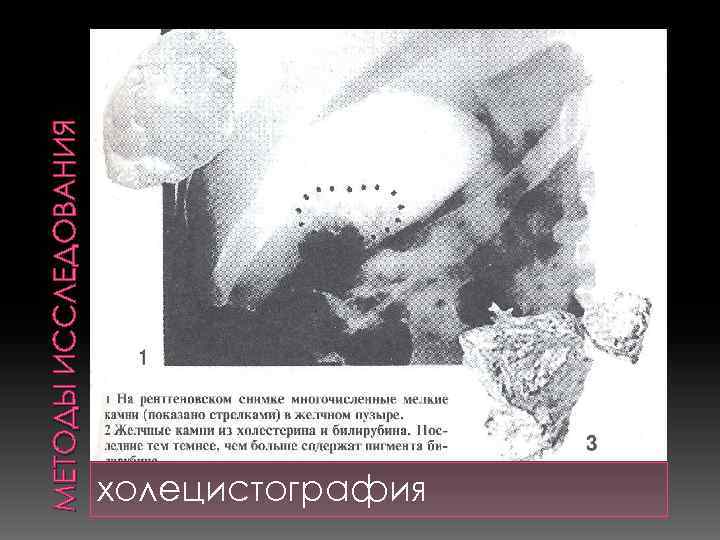

МЕТОДЫ ИССЛЕДОВАНИЯ холецистография

МЕТОДЫ ИССЛЕДОВАНИЯ холецистография